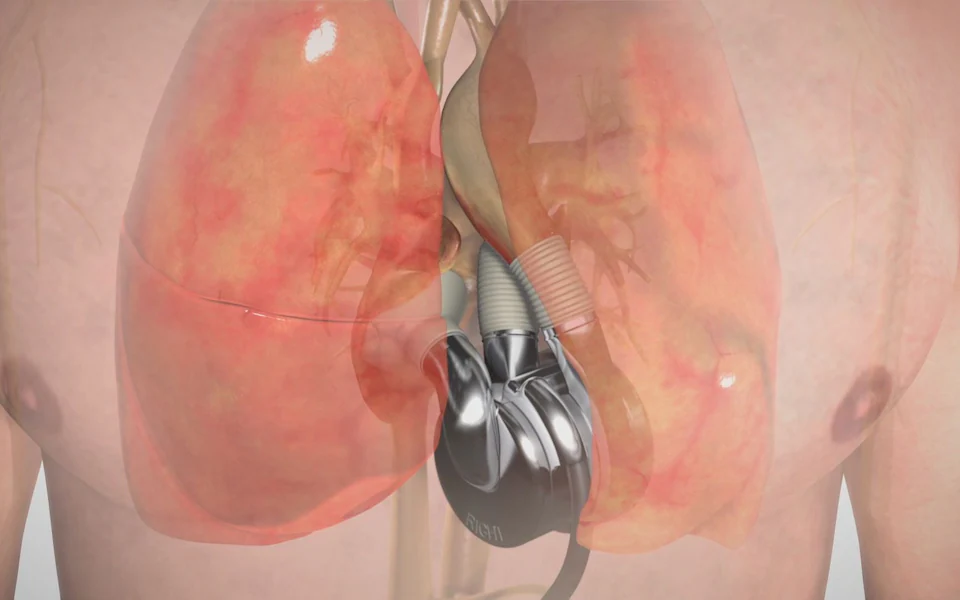

Η συσκευή, που ζυγίζει μόλις 600 γραμμάρια, εμφυτεύτηκε πρόσφατα σε ασθενή στο Σίδνεϊ, ο οποίος κατάφερε να επιστρέψει στο σπίτι του και να ζήσει για περισσότερες από 100 ημέρες μέχρι να λάβει τελικά μια ανθρώπινη καρδιά.

Η συσκευή, κατασκευασμένη από την εταιρεία του Timms, BiVACOR, με το μοναδικό μέταλλο που δεν απορρίπτεται από τον ανθρώπινο οργανισμό, έγινε παγκοσμίως γνωστή τον προηγούμενο μήνα όταν αποκαλύφθηκε πως ένας ασθενής στο Σίδνεϊ έγινε ο πρώτος άνθρωπος στον κόσμο που πήρε εξιτήριο από νοσοκομείο με τη συσκευή εμφυτευμένη.

Έζησε με τη συσκευή για περισσότερες από 100 ημέρες, πριν υποβληθεί σε μεταμόσχευση ανθρώπινης καρδιάς.

Ο στόχος όμως του Timms δεν είναι να χρησιμοποιείται η συσκευή μόνο προσωρινά.

Θέλει να καταργήσει εντελώς τις μεταμοσχεύσεις με δότες.

Η συσκευή, που ζυγίζει 600 γραμμάρια, είναι ακόμα μεγάλη για παιδιά, αλλά υπόσχεται να μειώσει τον πόνο της προσμονής για δεύτερη μεταμόσχευση.

«Αυτό το δοκιμαστικό είναι μόνο το πρώτο βήμα», λέει. «Θέλουμε οι ασθενείς να τη βάζουν και να μην επιστρέφουν ποτέ – να τη φορούν για μια ζωή.»

Η συσκευή, που ζυγίζει μόλις 600 γραμμάρια, εμφυτεύτηκε πρόσφατα σε ασθενή στο Σίδνεϊ, ο οποίος κατάφερε να επιστρέψει στο σπίτι του και να ζήσει για περισσότερες από 100 ημέρες μέχρι να λάβει τελικά μια ανθρώπινη καρδιά.

Η συσκευή, κατασκευασμένη από την εταιρεία του Timms, BiVACOR, με το μοναδικό μέταλλο που δεν απορρίπτεται από τον ανθρώπινο οργανισμό, έγινε παγκοσμίως γνωστή τον προηγούμενο μήνα όταν αποκαλύφθηκε πως ένας ασθενής στο Σίδνεϊ έγινε ο πρώτος άνθρωπος στον κόσμο που πήρε εξιτήριο από νοσοκομείο με τη συσκευή εμφυτευμένη.

Έζησε με τη συσκευή για περισσότερες από 100 ημέρες, πριν υποβληθεί σε μεταμόσχευση ανθρώπινης καρδιάς.

Ο στόχος όμως του Timms δεν είναι να χρησιμοποιείται η συσκευή μόνο προσωρινά.

Θέλει να καταργήσει εντελώς τις μεταμοσχεύσεις με δότες.

Η συσκευή, που ζυγίζει 600 γραμμάρια, είναι ακόμα μεγάλη για παιδιά, αλλά υπόσχεται να μειώσει τον πόνο της προσμονής για δεύτερη μεταμόσχευση.

«Αυτό το δοκιμαστικό είναι μόνο το πρώτο βήμα», λέει. «Θέλουμε οι ασθενείς να τη βάζουν και να μην επιστρέφουν ποτέ – να τη φορούν για μια ζωή.»